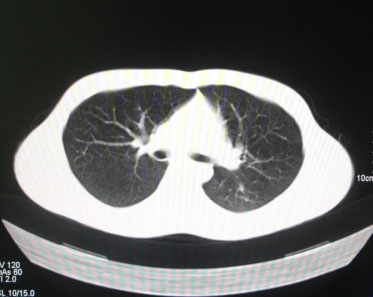

标题: CT26938:单发肺窗

病人17岁。咳嗽伴血丝痰2年?外院x片示左上肺椭圆形影,疑胸腺瘤

左肺尖见占位,建议上传纵隔窗及向上扫描。

左上纵隔占位性病变?